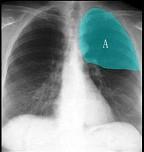

如图所示正常胸部X线影像图像上,该英文字母所代表的肺段为 ( )A.尖段B.后段C.尖后段D.舌叶上段E.前段

问题 如图所示正常胸部X线影像图像上,该英文字母所代表的肺段为 ( )

选项 A.尖段 B.后段 C.尖后段 D.舌叶上段 E.前段

答案 C